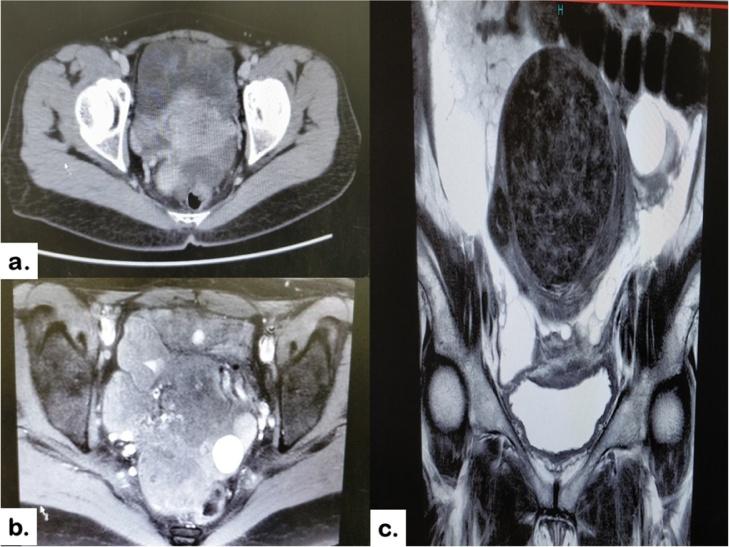

A 47 year old lady evaluated for peri-menopausal disturbance was diagnosed to have a multicystic lesion in the pelvis. With a preoperative suspicion of diagnosis of pseudomyxoma peritonei, CRS with HIPEC was planned. On exploration a diffuse multicystic mass was found in omentum and pouch of douglas with typical morphological features of MCPM. Complete cytoreduction was achieved with anterolateral and sub-diaphragmatic peritonectomy, omentectomy and panhystrectomy. HIPEC was performed with cisplatin 50 mg/m for 40 min. Pathological examination revealed MCPM of omentum and uterine surface with focal clusters of mesothelial proliferation. However there was low proliferative activity 1-2 %.

一名47岁因围绝经期紊乱接受评估的女性被诊断为盆腔有一个多囊性病变。术前怀疑为腹膜假黏液瘤,计划行CRS联合HIPEC。术中探查发现大网膜和Douglas窝有弥漫性多囊性肿块,具有多囊性腹膜间皮瘤的典型形态特征。通过前外侧和膈下腹膜切除术、大网膜切除术和全子宫切除术实现了根治性细胞减灭。顺铂50mg/m²进行40分钟的HIPEC治疗。病理检查显示大网膜和子宫表面为多囊性腹膜间皮瘤,有局灶性间皮细胞增生簇。然而,增殖活性较低,为1%-2%。